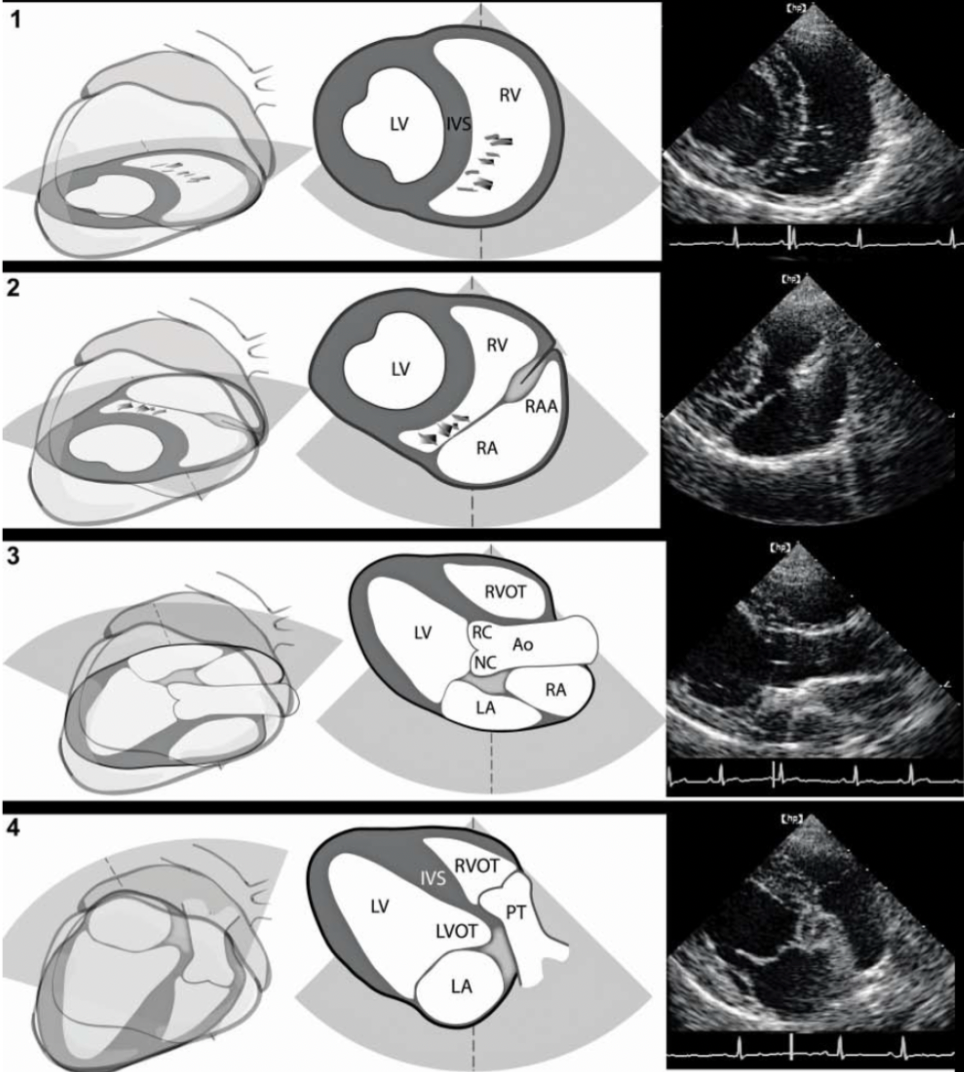

Name the ECHO VIEW and STRUCTURES

RPS LONG AXIS

LPS SHORT AXIS

LPS LONG AXIS